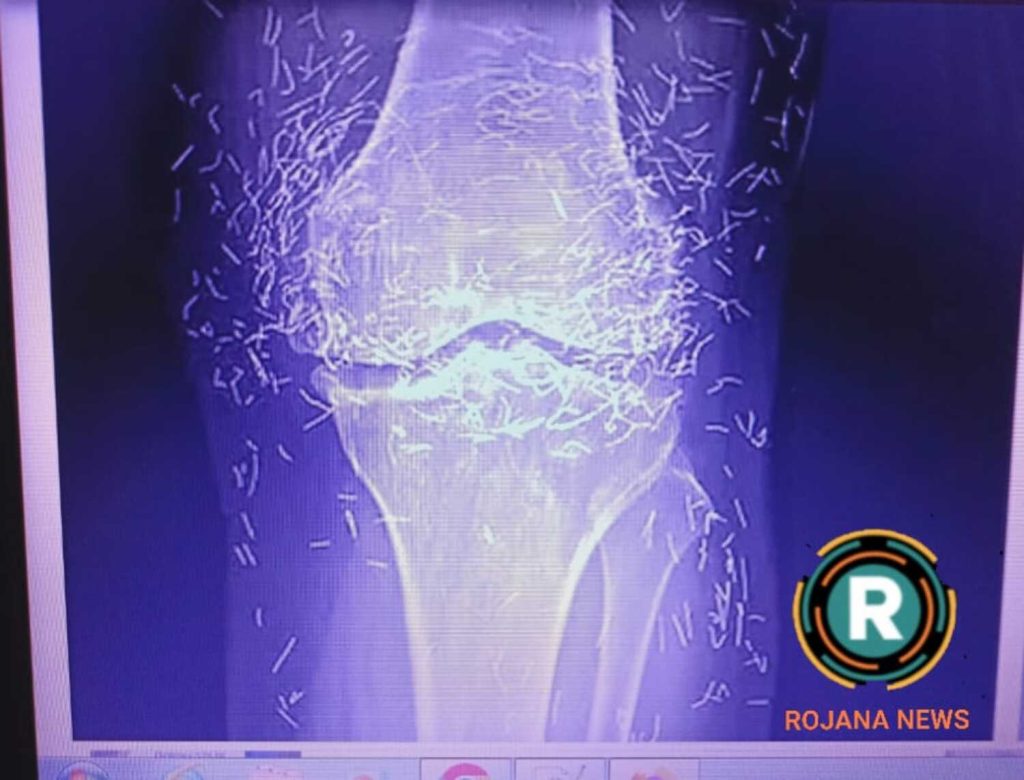

कल्पना कीजिए, महिला के जोड़ों में मिला सैकड़ों सोने की सुइयां? चौंकाने वाला सच!, जानकर उड़ जाएंगे होश! एक महिला घुटनों के दर्द से परेशान है, डॉक्टर के पास जाती है, एक्स-रे होता है और पता चलता है कि उसके घुटनों में सैकड़ों सोने के तार या सुइयां जड़ी हुई हैं! हां, यह कोई फिल्म की स्क्रिप्ट नहीं, बल्कि दक्षिण कोरिया की एक 65 साल की महिला की असली कहानी है। इस घटना ने न सिर्फ मेडिकल जगत को चौंकाया,एक्यूपंक्चर जैसी वैकल्पिक चिकित्सा पद्धतियों पर भी सवाल खड़े कर दिए।

चौंकाने वाली हकीकत से रूबरू करा दे तो? ऐसा ही हुआ दक्षिण कोरिया की एक महिला के साथ। उनके घुटनों के दर्द की जांच के दौरान जब एक्स-रे और स्कैन किए गए, तो डॉक्टर भी हैरान रह गए। उनके जोड़ों में ‘सोने के तार’ (Gold Threads) मिले।

महिला के जोड़ों में मिला सैकड़ों सोने की सुइयां? चौंकाने वाला सच!, जानकर उड़ जाएंगे होश! महिला के जोड़ों में मिला सैकड़ों सोने की सुइयां? चौंकाने वाला सच!, जानकर उड़ जाएंगे होश! हर हफ्ते एक्यूपंक्चर सेशन लेती थीं, और जब दर्द ज्यादा होता तो और भी ज्यादा। लेकिन समय बीतने के साथ दर्द कम होने की बजाय और बढ़ गया। आखिरकार, वे डॉक्टर के पास गईं, और डॉक्टरों ने एक्स-रे करवाया। एक्स-रे देखकर सब हैरान रह गए – महिला के जोड़ों में मिला सैकड़ों सोने की सुइयां? चौंकाने वाला सच!, जानकर उड़ जाएंगे होश! घुटनों के आसपास सैकड़ों छोटी-छोटी सोने की सुइयां दिख रही थीं! ये सुइयां इतनी ज्यादा थीं

एक्स-रे और एमआरआई स्कैन में डॉक्टरों ने पाया कि महिला के जोड़ों के आसपास छोटे-छोटे सोने के तार मौजूद हैं।

महिला के जोड़ों में मिला सैकड़ों सोने की सुइयां? चौंकाने वाला सच!, जानकर उड़ जाएंगे होश! जब एक्स-रे हुआ, तो डॉक्टरों को लगा कि ये कोई मेटल आर्टिफैक्ट हैं, लेकिन जांच से पता चला कि ये गोल्ड नीडल्स हैं। बोस्टन यूनिवर्सिटी के रेडियोलॉजिस्ट डॉ. अली गुएर्माजी, जो इस केस से जुड़े नहीं थे, ने कहा कि शरीर में सुइयां छोड़ने से इंफ्लेमेशन, एब्सेस या इंफेक्शन हो सकता है। शरीर इसे विदेशी मानकर उसके चारों ओर फाइब्रस टिशू बना लेता है, महिला के जोड़ों में मिला सैकड़ों सोने की सुइयां? चौंकाने वाला सच!, जानकर उड़ जाएंगे होश! जो दर्द बढ़ा सकता है।और बड़ा खतरा – एमआरआई स्कैन। महिला के जोड़ों में मिला सैकड़ों सोने की सुइयां? चौंकाने वाला सच!, जानकर उड़ जाएंगे होश! अगर एमआरआई कराना पड़े, तो मैग्नेटिक फील्ड से सुइयां हिल सकती हैं महिला के जोड़ों में मिला सैकड़ों सोने की सुइयां? चौंकाने वाला सच!, जानकर उड़ जाएंगे होश!महिला के जोड़ों में मिला सैकड़ों सोने की सुइयां? चौंकाने वाला सच!, जानकर उड़ जाएंगे होश! और कोई नस या धमनी डैमेज कर सकती हैं।महिला के जोड़ों में मिला सैकड़ों सोने की सुइयां? चौंकाने वाला सच!, जानकर उड़ जाएंगे होश! के केस में, एक्स-रे से ही डायग्नोसिस मुश्किल हो गया क्योंकि सुइयां एनाटॉमी को छिपा रही थीं। डॉक्टरों ने सलाह दी कि ऐसी थेरेपी से बचें, क्योंकि रिस्क ज्यादा हैं

1- एक्स-रे में साफ दिखा कि उनके जोड़ों के आसपास जाले जैसी संरचना बनी हुई थी।